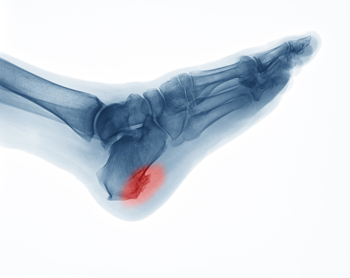

Sever’s disease, also known as calcaneal apophysitis is a common bone disorder that occurs during childhood. The disease is defined as an inflammation of the growth plate in the heel. When a child has a growth spurt, his heel bone grows faster than the muscles, tendons, and ligaments in his leg. This disease is a result of overuse. The people who are most likely to be affected by this disease are children who are in a growth spurt, especially boys who are from the ages of 5 to 13 years old. 60% of children with Sever’s disease have both heels involved.

Your doctor will diagnose your child based on his or her symptoms, x-rays are generally not helpful in diagnosing this disease. Your doctor may examine both heels and ask your child questions about his or her activity level in sports. Your doctor may then use the squeeze test on your child’s heel to see if there is any pain. Nevertheless, some doctors might still use x-rays to rule out any other issues such as fractures, infections, and tumors.

Sever’s disease occurs when part of the child’s heel known as the growth plate (calcaneal epiphysis) is attached to the Achilles tendon. This area can suffer injury when the muscles and tendons of the growing foot do not keep pace with bone growth. Therefore, the constant pain which one experiences at the back of the heel will make the child unable to put any weight on the heel. The child is then forced to walk on their toes.